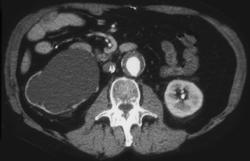

Obstructing Left Distal Calculus in Ureter